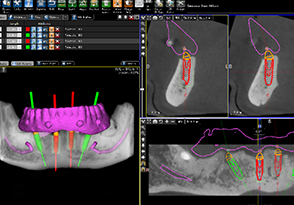

1.CT数据导入

2.成像预览

3.添加放射导板数据

4.尽量让每一对匹配点角度一致

5.种植模拟设计

6.自动生成报告及进行数据输出

7.导板设计(分层导板-美尚专利)